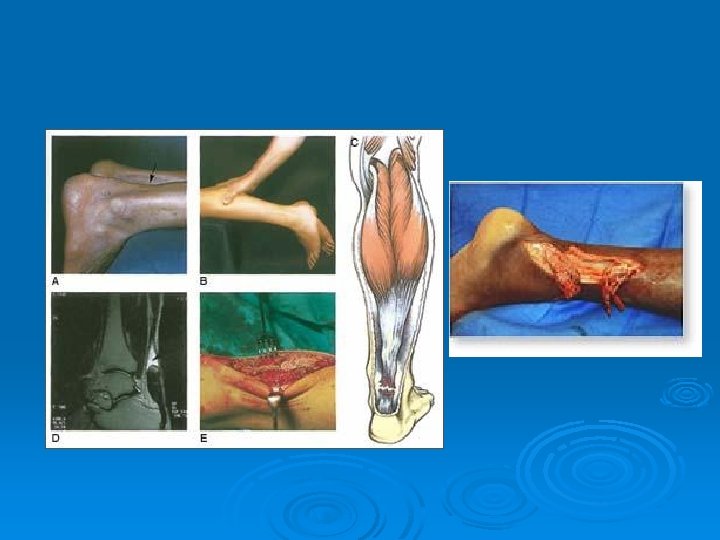

Achilles Tendon Rupture Ø MX: l Ø S/S: l Ø Feel or hear a pop. Feel as if they’ve been kicked in the leg. Inability to plantar flex foot. TX: l Ø Sudden, forceful plantar flexion of the ankle with a chronically tight tendon. Surgery or a cast Prevention: l Stretching and proper care of any tendonitis